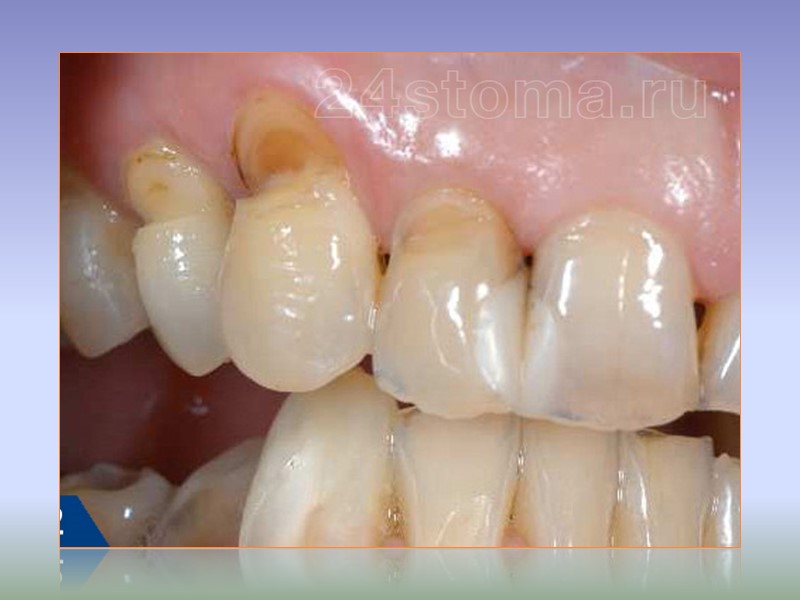

Классификация по локализации: Фиссурный кариес. Контактный (апроксимальный) кариес. Пришеечный (цервикальный) кариес. Циркулярный (кольцевой) кариес.

Поверхностный кариес дифференцируют с: Системной гипоплазией (бороздчатая форма) Флюорозом (эрозивная форма) Эрозией эмали Клиновидным дефектом Кислотным некрозом

Дифференциальная диагностика поверхностного кариеса с эрозией эмали и клиновидным дефектом Общее: - жалобы на эстетический дефект; - кратковременные боли от химических, термических раздражителей; - возникновение после прорезывания зуба; - прогрессирующее течение; - наличие дефекта твердых тканей зуба в пределах эмали; - болезненное зондирование.

Дифференциальная диагностика среднего кариеса Средний кариес дифференцируют с: 1. поверхностным кариесом; 2. глубоким кариесом; 3. клиновидным дефектом; 4. эрозией твердых тканей; 5. некрозом твердых тканей зуба; 6. хроническим периодонтитом.